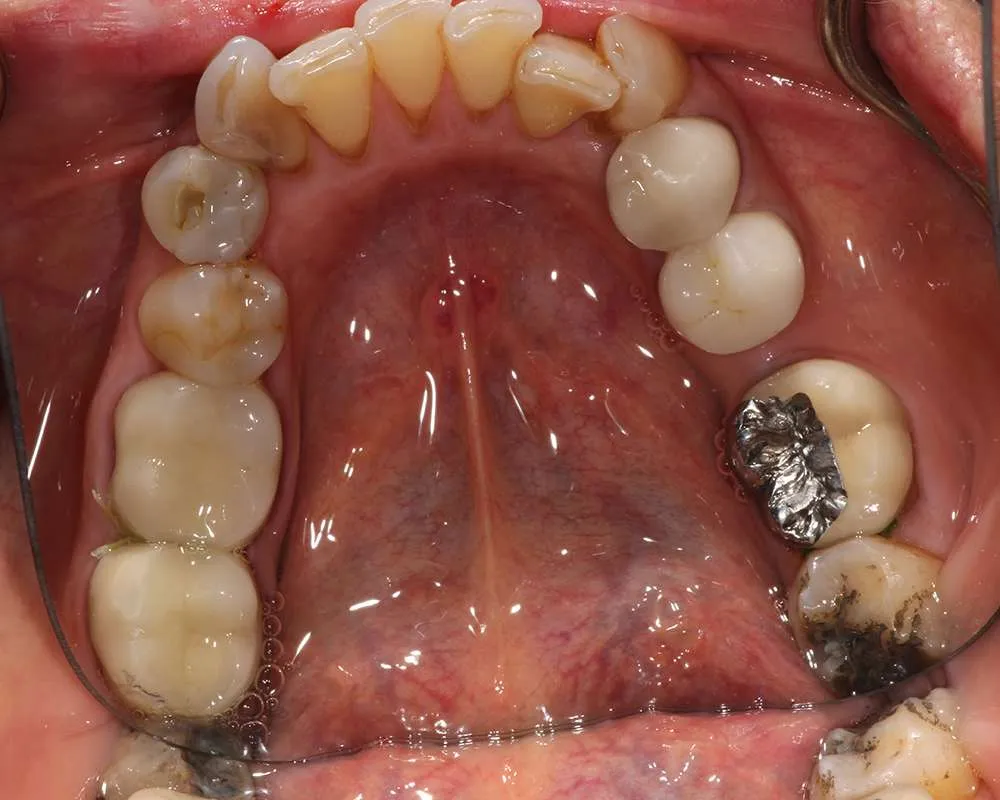

Real Stories, Real Results: Case Studies Showcasing How Our Personalized Approach Transforms Smiles and Lives

Complex Cases

Witness the Remarkable Changes We Can Achieve